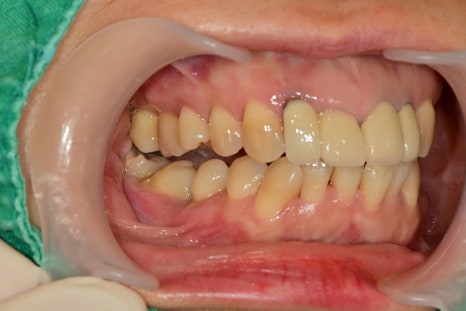

치과치료가 두려워서 치료를 미루고 계셨던 환자분께서 가족소개로 내원해 주셨습니다.

아래 어금니가 3개가 발치된 상황에서 오랜 시간 지남에 따라 아래쪽은 어금니가 쓰러져있었고,

위쪽 치아는 아래에서 서포트해주는 치아가 없기 때문에 아래쪽으로 정출되어 있는 상태였습니다.

치아의 쓰러짐과 정출된 정도가 너무 심했기 때문에 임플란트 수술을 위해서 해당 치아들의 발치가 불가피했습니다.